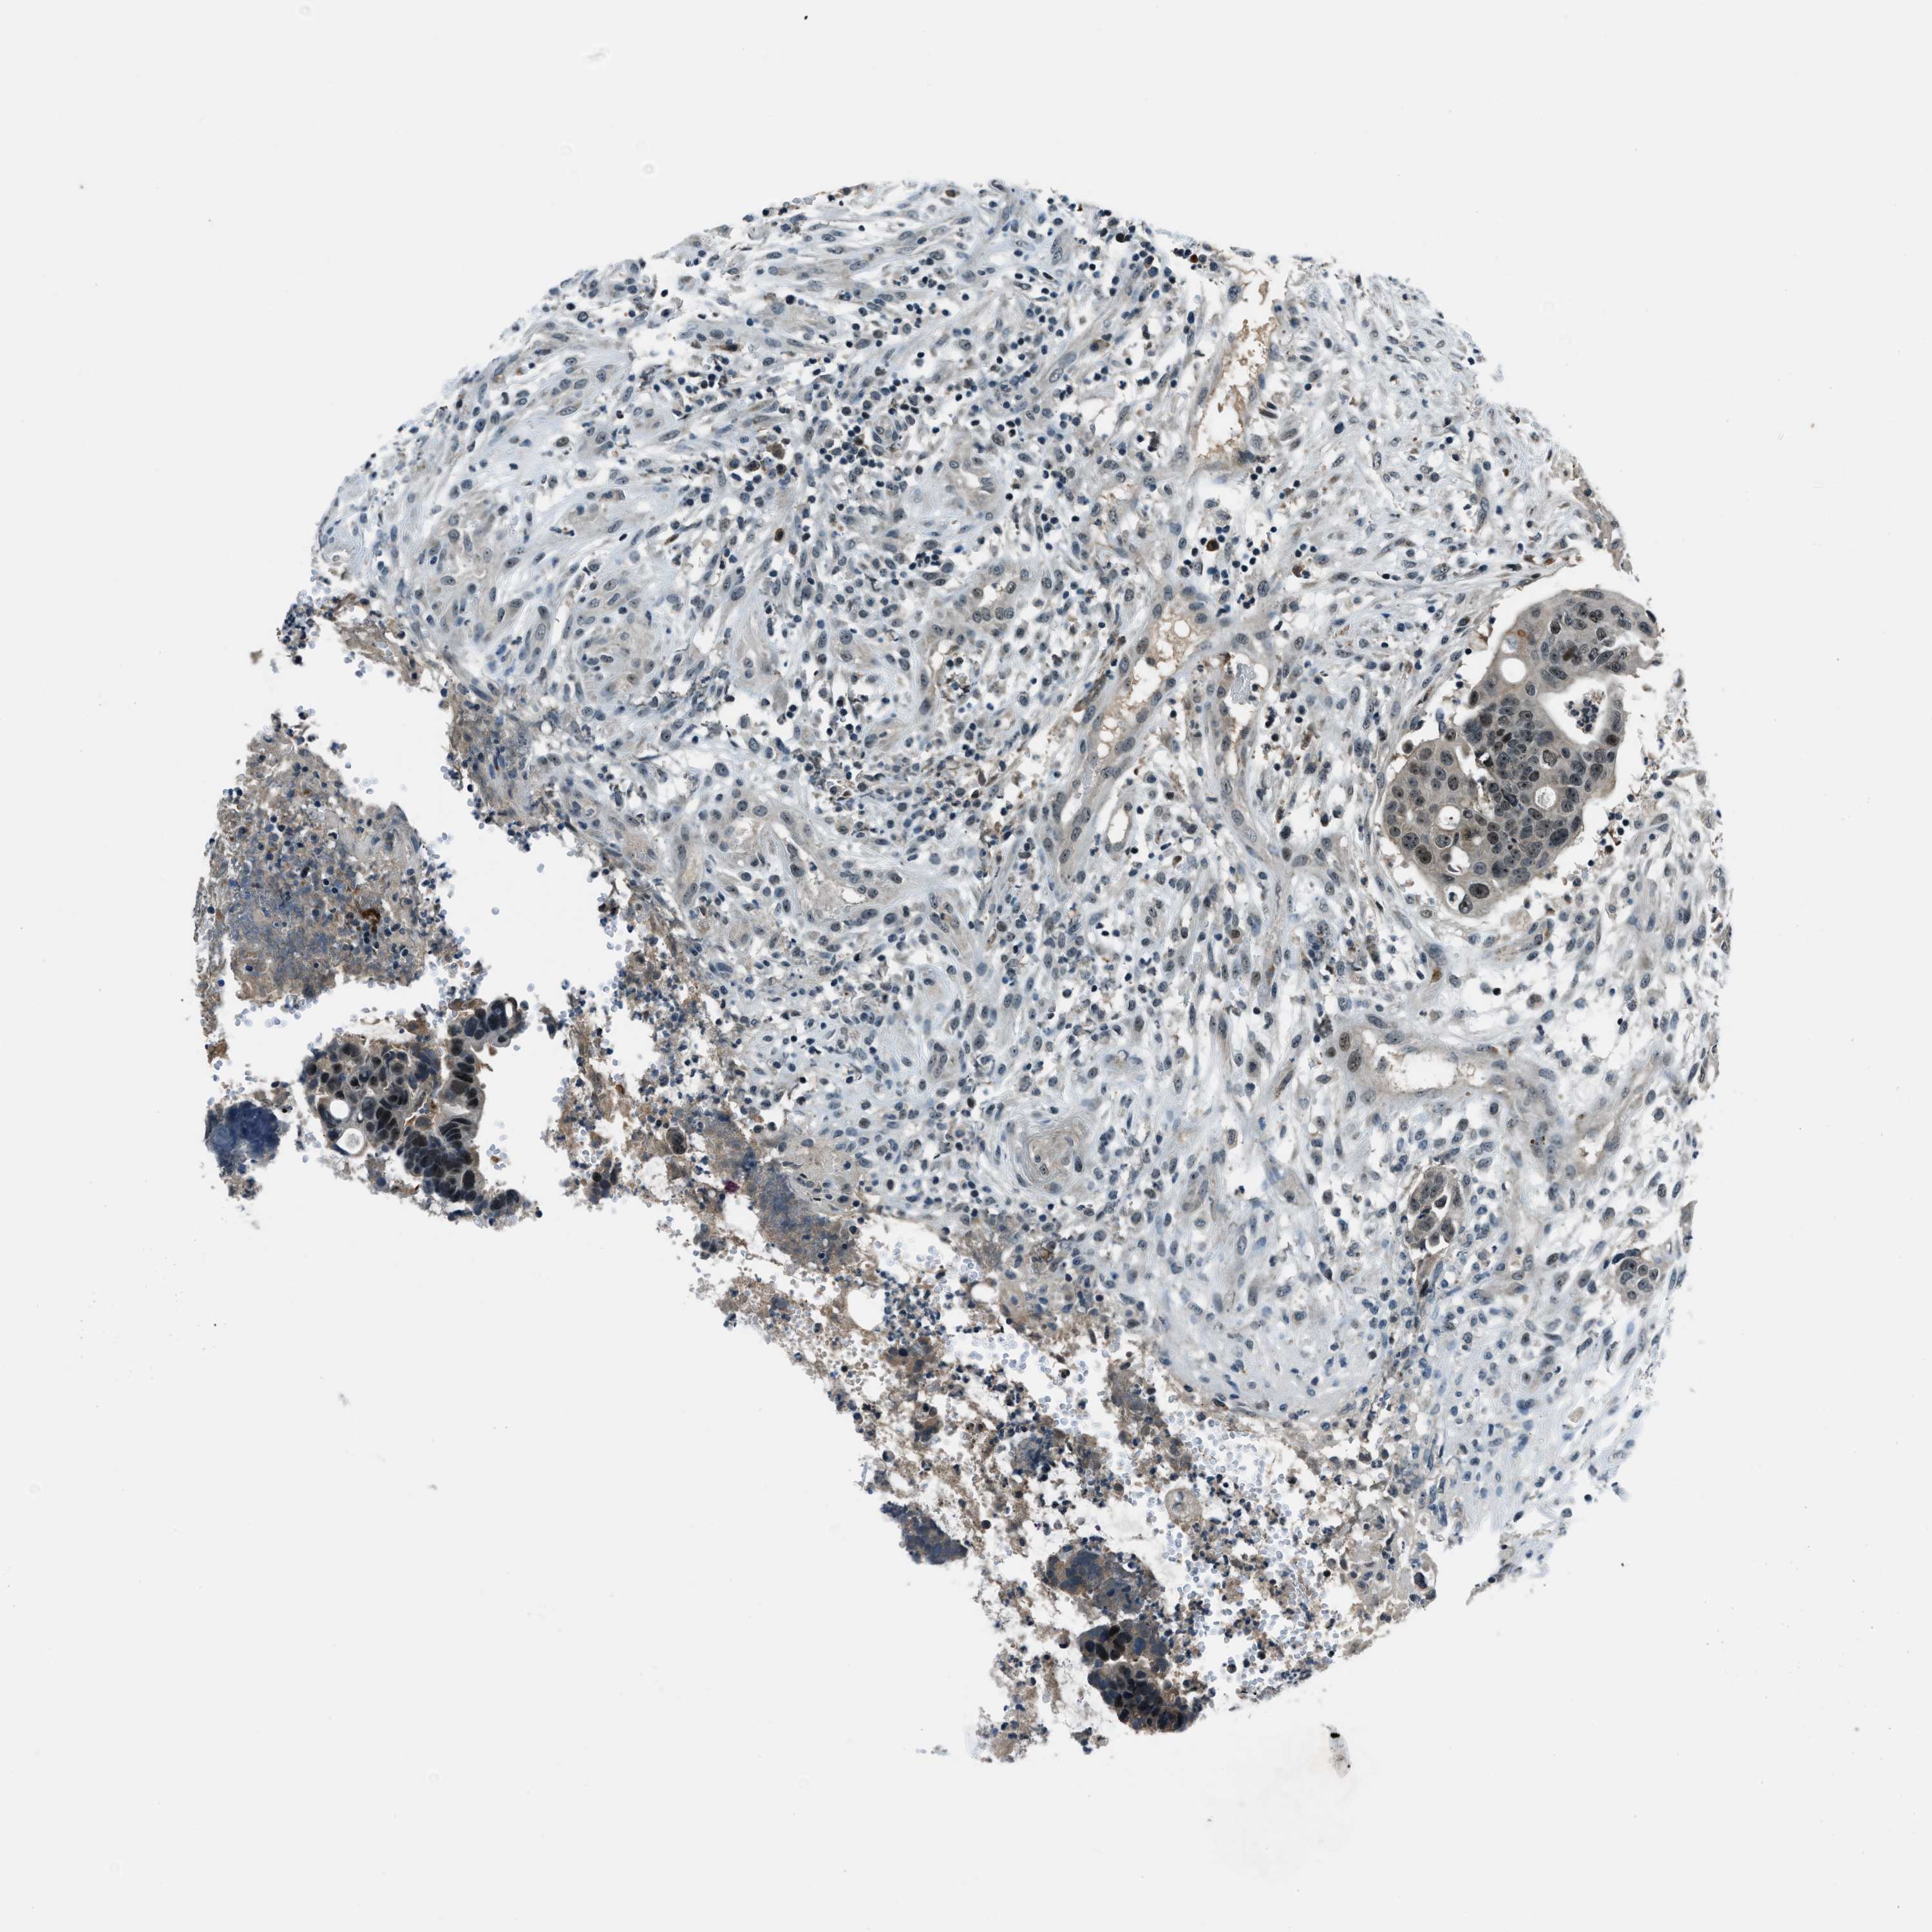

CANCER COLORECTAL CANCER Show tissue menu

Colorectal cancer

Human cancer

Colon adenocarcinoma